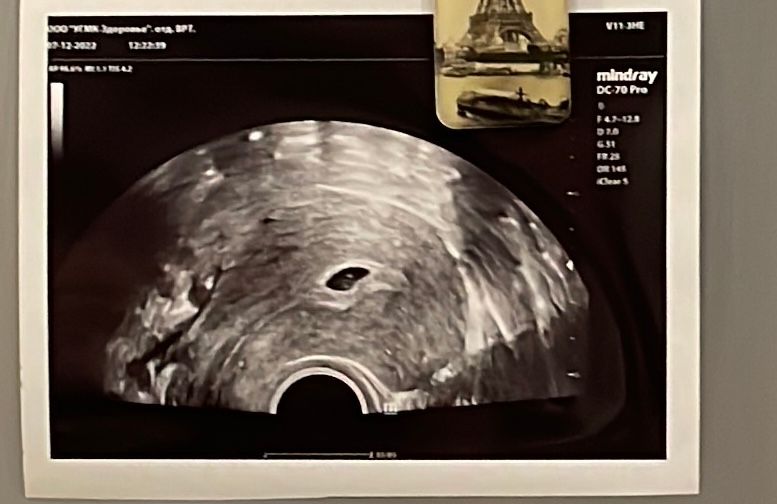

23 дпп узи